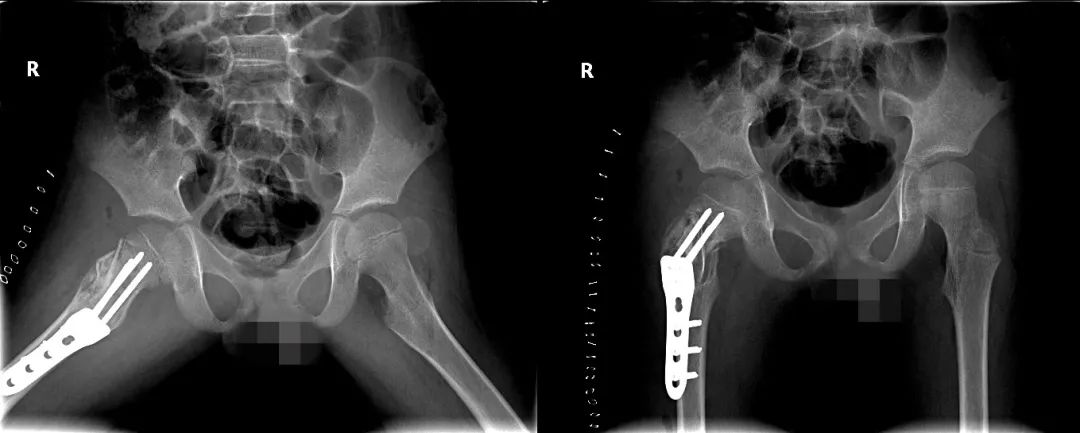

所幸,小武术后的病理结果是良性,最终确诊是动脉瘤样骨囊肿。目前,他身体恢复得也不错,伤口愈合很好,在支具的保护下已经可在床边站立,现在逐步开始试着走路了。

(小武髋部的骨肿瘤切掉后,植入了内固定的器具。南方医科大学中西医结合医院供图)等再过一段时间复查X线,如果医生能看到新生的骨慢慢填满骨腔,小武就可以拆掉支具了,开始日常活动了。床边走走、出去散散步等,都没问题。

等植骨和骨折处完全愈合后,他的右腿就基本能恢复正常活动了,跑跑跳跳、球类运动等都不受影响,身体发育和长个子也都没问题。